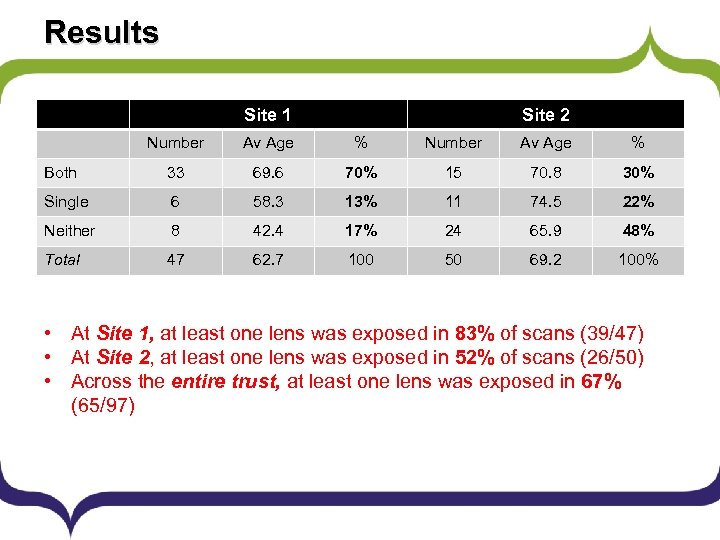

Results Site 1 Site 2 Number Av Age % Both 33 69. 6 70% 15 70. 8 30% Single 6 58. 3 13% 11 74. 5 22% Neither 8 42. 4 17% 24 65. 9 48% Total 47 62. 7 100 50 69. 2 100% • At Site 1, at least one lens was exposed in 83% of scans (39/47) • At Site 2, at least one lens was exposed in 52% of scans (26/50) • Across the entire trust, at least one lens was exposed in 67% (65/97)

Results § As a trust, we were failing to meet the irradiation § § standard that patient lenses should be avoided during CT head examinations. Scanning at Site 2 was closer to the standard than at Site 1. This may have been related to the types of cases scanned. At both sites, the lenses of younger patients were scanned less often than those of older patients.